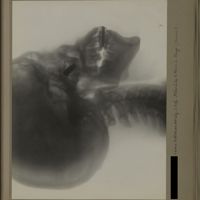

Ensemble de radiographies destinées à localisation de corps étrangers (crâne, tronc, membres). Fonds Guy et Marie-José Pallardy